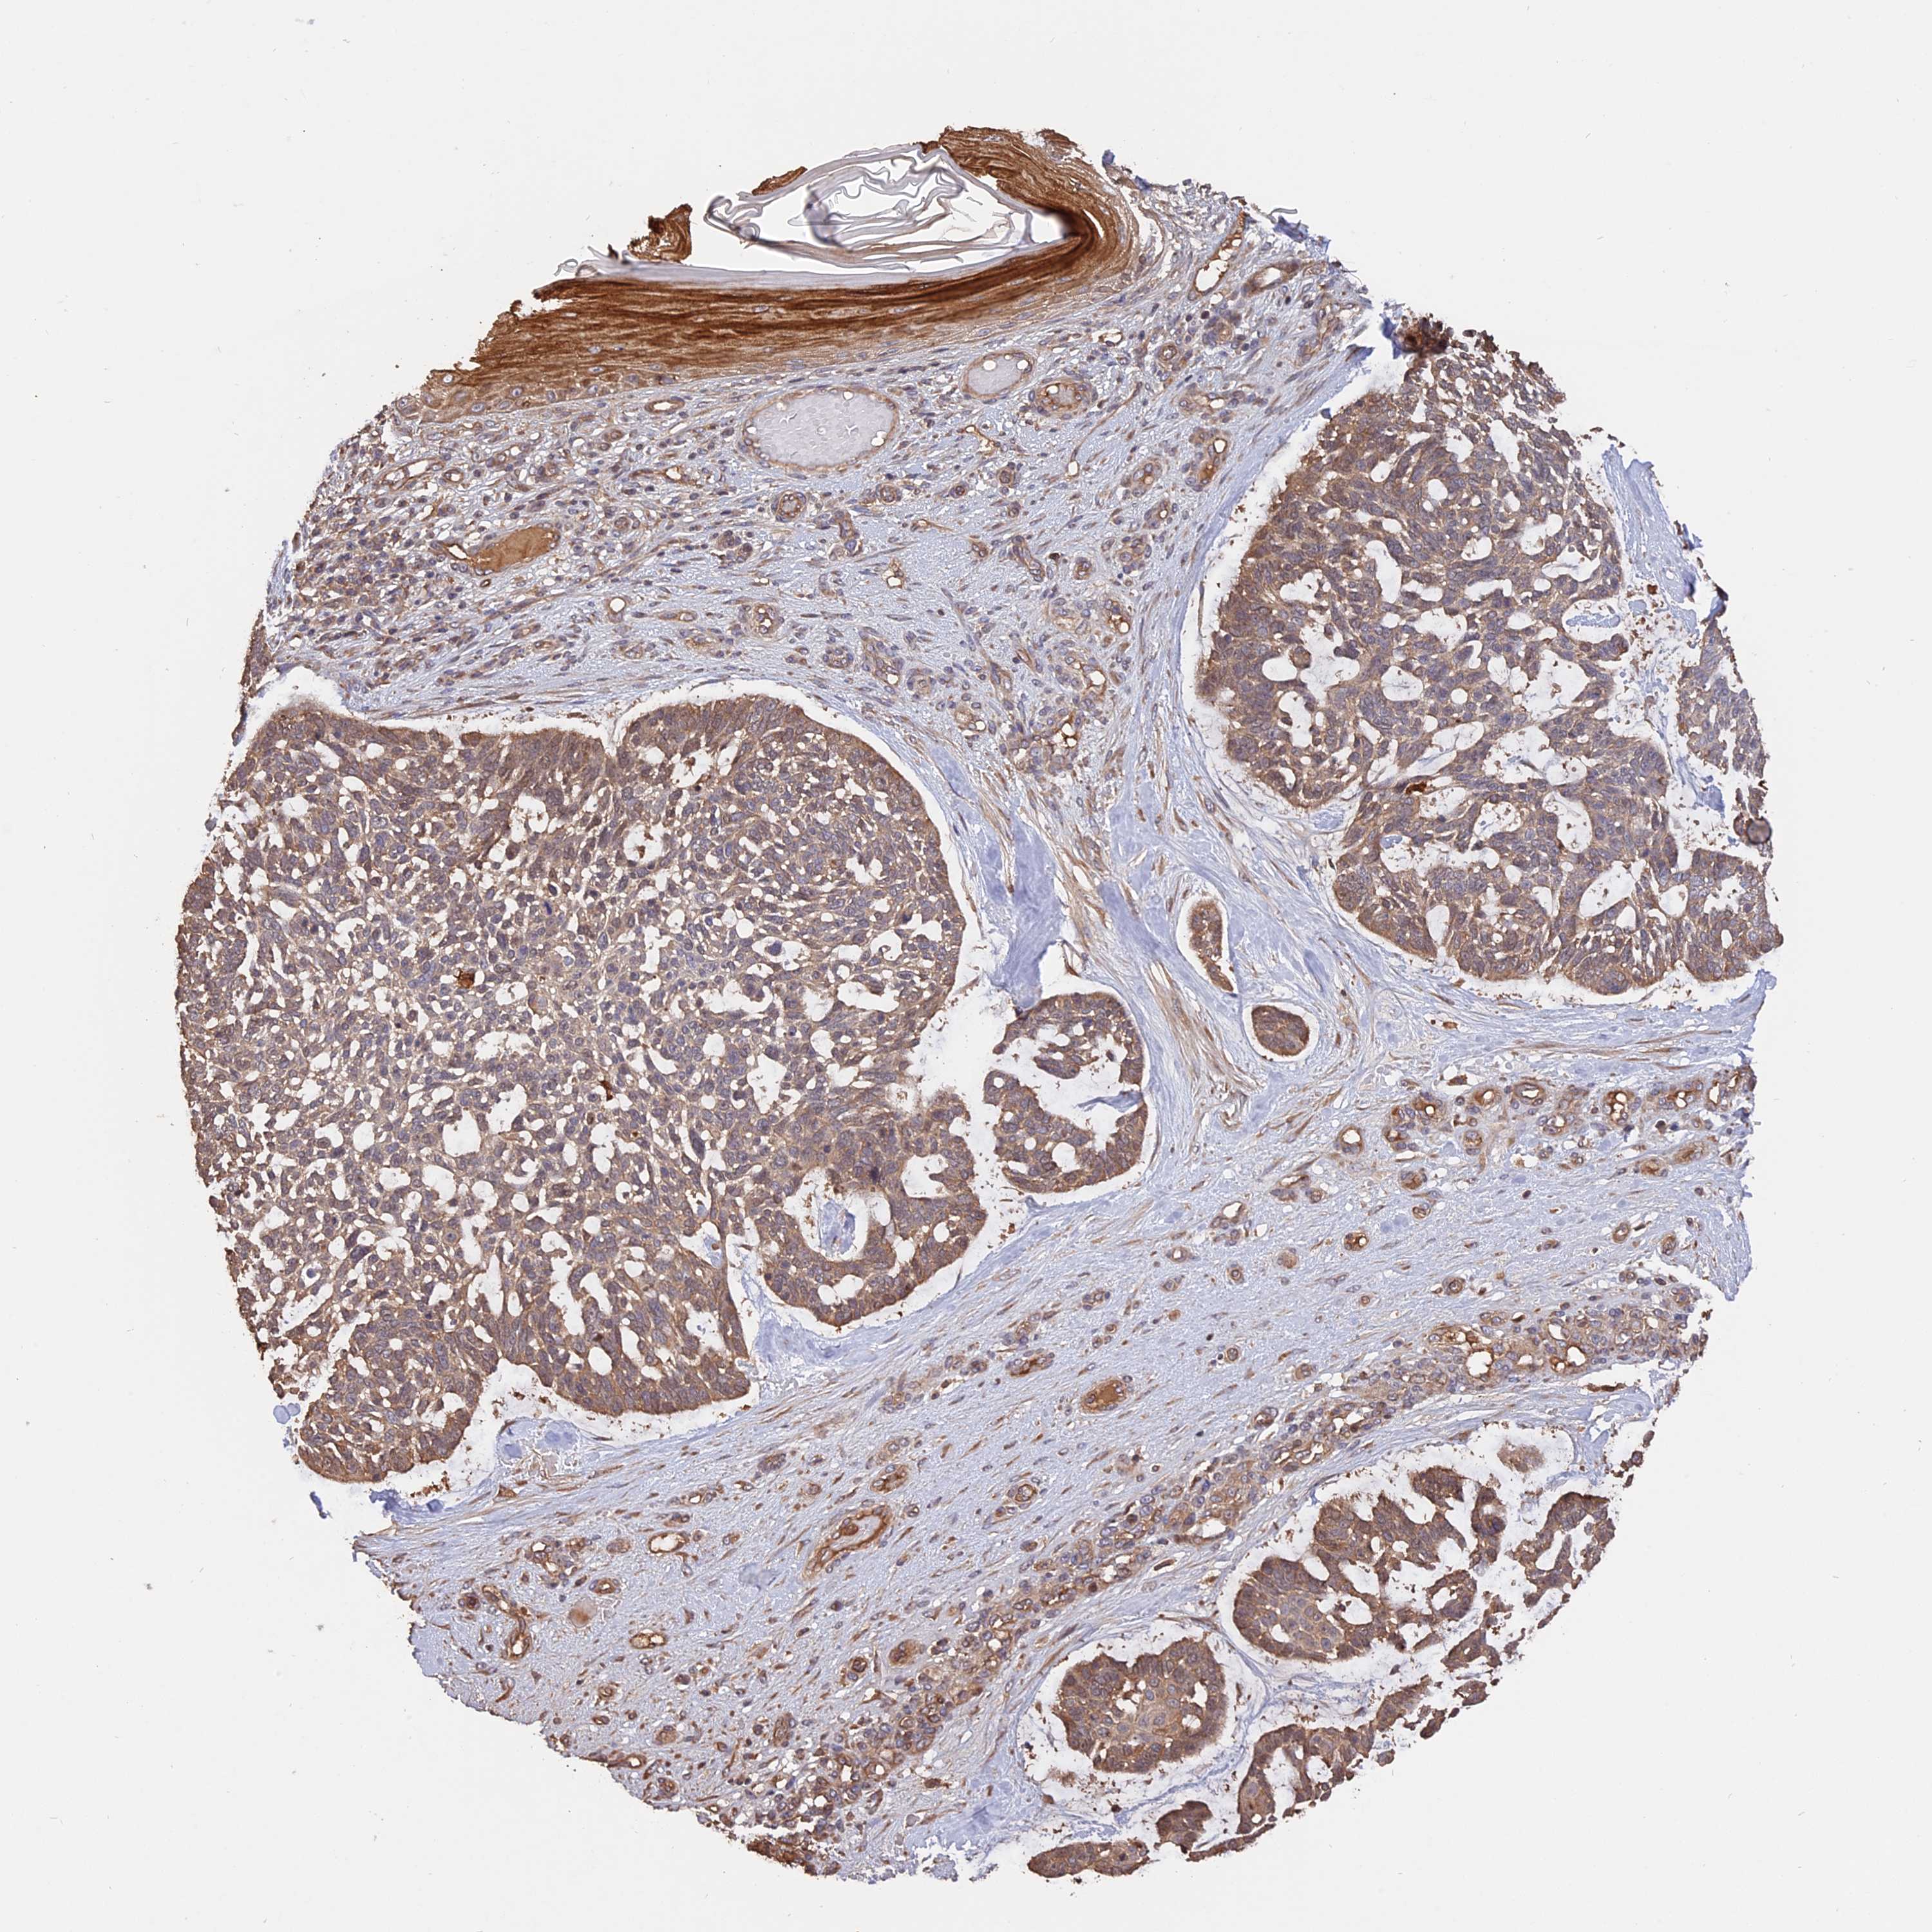

SKIN CANCER - Protein expressioni

A mouse-over function shows sample information and annotation data. Click on an image to view it in a full screen mode. Samples can be filtered based on level of antibody staining by selecting one or several of the following categories: high, medium, low and not detected. The assay and annotation is described here.

Antibody staining in the annotated cell types in the current human tissue is reported as not detected, low, medium, or high, based on conventional immunohistochemistry profiling in selected tissues. This score is based on the combination of the staining intensity and fraction of stained cells.

Each image is clickable and will lead to virtual microscopy that enables deeper exploration of all samples and also displays staining intensity scores, fraction scores and subcellular localization as well as patient and tissue information for each sample.

Antibody HPA041650

Staining

High

Intensity

Strong

Quantity

>75%

Location

Nuclear

Basal cell carcinoma

Squamous cell carcinoma, NOS

Squamous cell carcinoma, metastatic, NOS